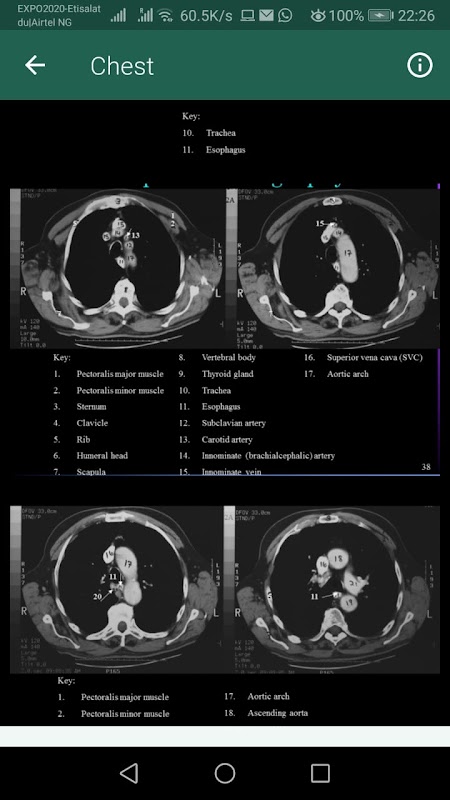

Una risorsa ideale per l'aula o l'ambiente clinico, Anatomia sezionale per professionisti dell'imaging, l'app fornisce un approccio completo e altamente visivo all'anatomia sezionale dell'intero corpo. Presentazioni affiancate di immagini diagnostiche reali da entrambe le modalità MRI e TC e corrispondenti disegni anatomici illustrano i piani anatomici più comunemente dimostrati dall'imaging diagnostico. Le descrizioni facili da seguire descrivono in dettaglio la posizione e la funzione dell'anatomia, mentre le immagini chiaramente etichettate aiutano a identificare con sicurezza le strutture anatomiche durante gli esami clinici. In tutto, è l'unico riferimento di cui hai bisogno per produrre costantemente le migliori immagini diagnostiche possibili.

La presentazione affiancata delle illustrazioni anatomiche e delle corrispondenti immagini TC e MRI chiarisce la posizione e la struttura dell'anatomia in sezione.

Più di 1.500 immagini di alta qualità e disegni al tratto dettagliati dimostrano l'anatomia in sezione per ogni piano corporeo comunemente ripreso in ambito clinico.

I disegni di riferimento e i corrispondenti piani di scansione vengono visualizzati su pagine appropriate con le immagini effettive, quindi sono facilmente consultabili per la correlazione tra i piani di scansione e le immagini risultanti.